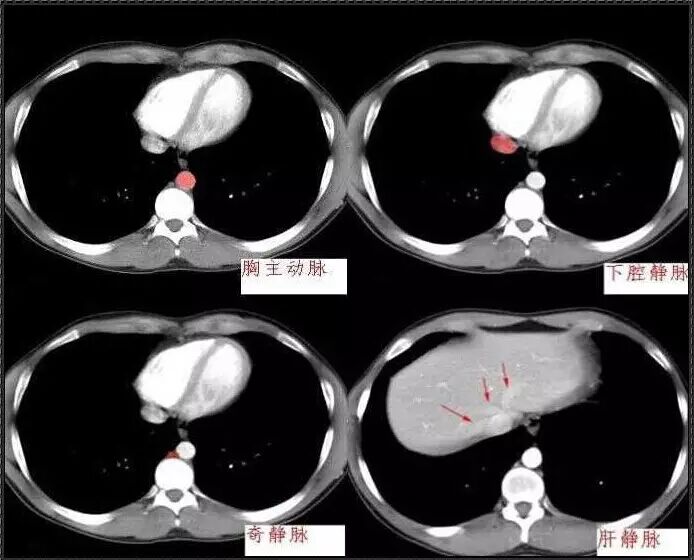

十分钟学会腹部CT解剖(多图)